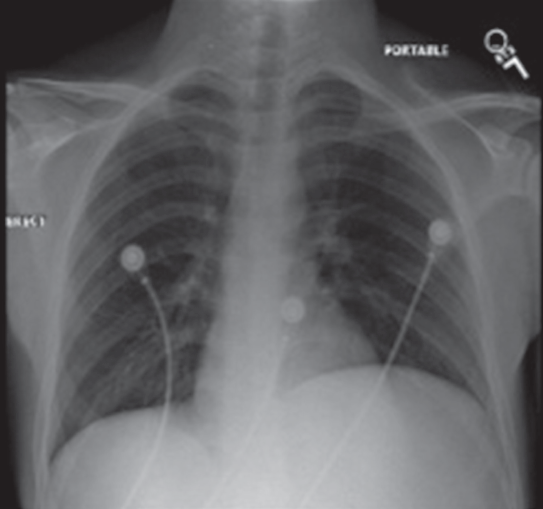

A 77-year-old woman presented with shortness of breath and intermittent left flank pain of 2- to 3-day duration.